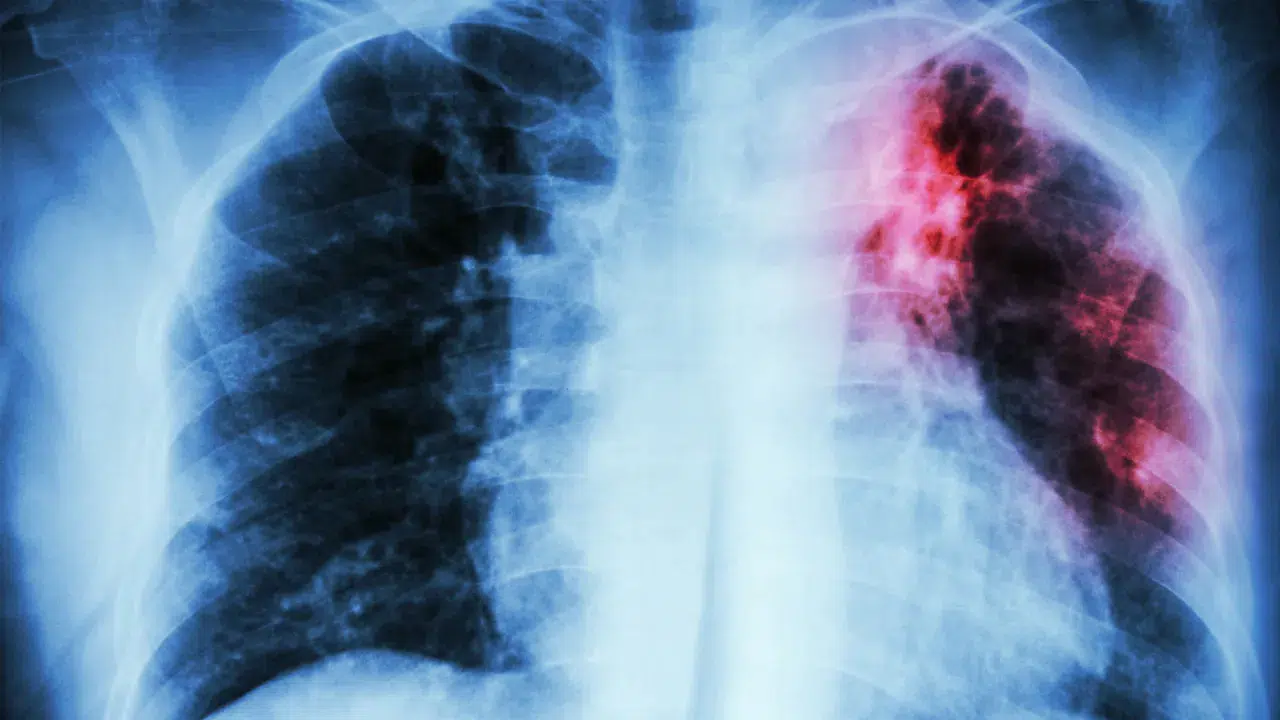

DSÖ: Tüberküloz her yıl 1,2 milyon can alıyor, azalan fonlar ilerlemeyi tehdit ediyor

Dünya Sağlık Örgütü, küresel tüberküloz vakalarının azalsa da finansman eksikliği nedeniyle mücadelede kazanımların risk altında olduğunu bildirdi.

Dünya Sağlık Örgütü (DSÖ), azalan küresel fonlamanın tüberkülozla mücadelede yıllardır kaydedilen ilerlemeyi tehlikeye attığını açıkladı. Kuruluşun 2025 Küresel Tüberküloz Raporu’na göre, hastalık her yıl 1,2 milyondan fazla insanın ölümüne ve yaklaşık 10,7 milyon kişinin enfekte olmasına neden oluyor.

Rapora göre, 2023-2024 yılları arasında tüberküloz enfeksiyonları yaklaşık %2 oranında azalırken, ölümler %3 oranında düştü. Ancak durgun finansman ve sağlık hizmetlerine eşitsiz erişim nedeniyle bu kazanımların kalıcılığı tehlikede.

DSÖ raporuna göre, 2024 yılında yeni tüberküloz vakalarının %87’si sadece 30 ülkede görüldü. Bunlar arasında Hindistan, Endonezya ve Filipinler gibi ülkeler öne çıkarken, bu üç ülke küresel vakaların üçte ikisinden fazlasını oluşturdu.

DSÖ, ülkeleri tüberkülozla mücadele için fonları artırmaya, sağlık sistemlerini güçlendirmeye ve eşit erişimi sağlamaya çağırdı. Uzmanlara göre, finansman açığı kapatılmazsa tüberkülozun kontrol altına alınması onlarca yıl gecikebilir.